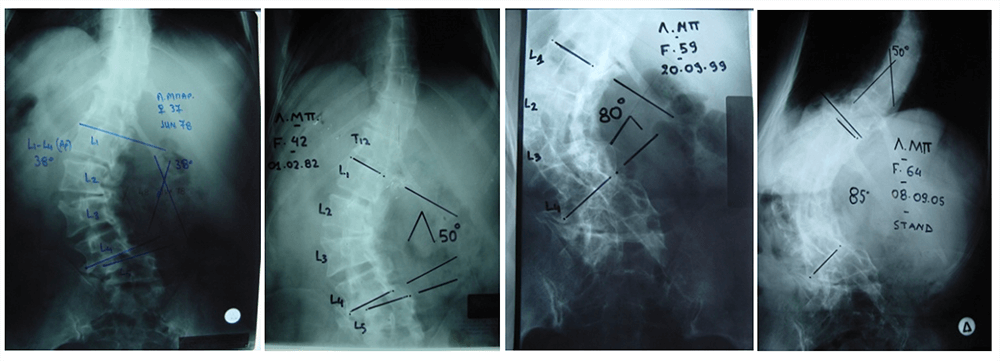

Είκ 2: (α,β) Προεγχειρητικές ακτινογραφίες της Σ.Σ. Προσθιοπίσθια και πλάγια, σε όρθια στάση.

Παρατηρείται ύπαρξη μεγάλης σκολιώσεως και κυφώσεως η οποίες έχουν οδηγήσει σε πλήρη αστάθεια και ανισορροπία του κορμού.

(γ,δ) Μετεγχειρητικές ακτινογραφίες της Σ.Σ. Προσθιοπίσθια και πλάγια, σε όρθια στάση.

Η ασθενής υποβλήθηκε σε χειρουργική επέμβαση για την αποκατάσταση της ισορροπίας του κορμού της και την εξάλειψη της παραμορφώσεως της Σ.Σ. Για το σκοπό αυτό έγινε σπονδυλοδεσία από τον 3ο θωρακικό σπόνδυλο μέχρι τα λαγόνια οστά.